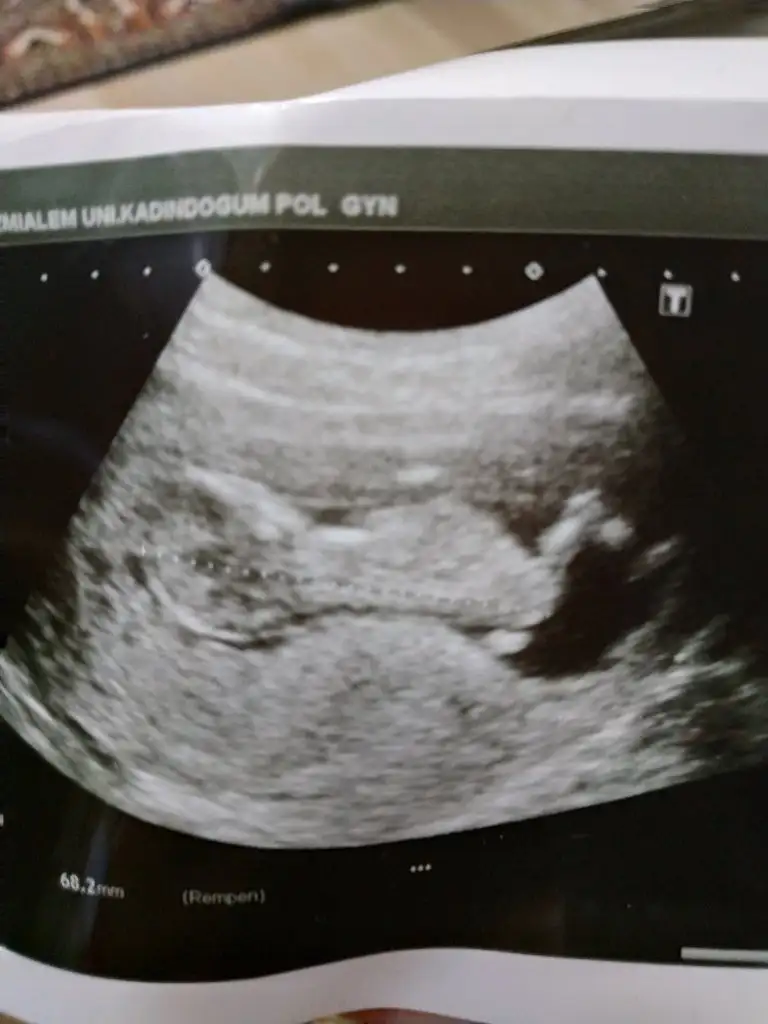

Kız sanki başka usg varmı 11+ yada 12+ olmalı100 de 100 kızım diye bağırıyor dimi kizlar:) yanılıyor muyum?11+1

Çelişkide mi kaldınız? Sizin yorumunuz benim için önemli.. Yok başka fotosu bi bu var. Zaten daha12 haftalık olmadiKız sanki başka usg varmı 11+ yada 12+ olmalı

Şimdilik kız diyorumÇelişkide mi kaldınız? Sizin yorumunuz benim için önemli.. Yok başka fotosu bi bu var. Zaten daha12 haftalık olmadi

Teşekkür ederim . İkisi de miKız bence

Aaaa ikiz mi anlamadımTeşekkür ederim . İkisi de mi![]()

Altta ki erkek sankiTeşekkür ederim . İkisi de mi![]()

Sağlıkla gelsin biri kız bi erkek diyorum

Ayy hadi inşallah hayırlısı ileAltta ki erkek sanki